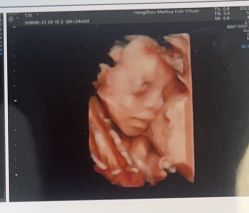

• 杭州贝瑞斯美华妇儿医院·早孕·产检·儿科

• -杭州贝瑞斯美华妇儿医院·早孕·产检·儿科

余笙 上传于 23-09-01 | 报错